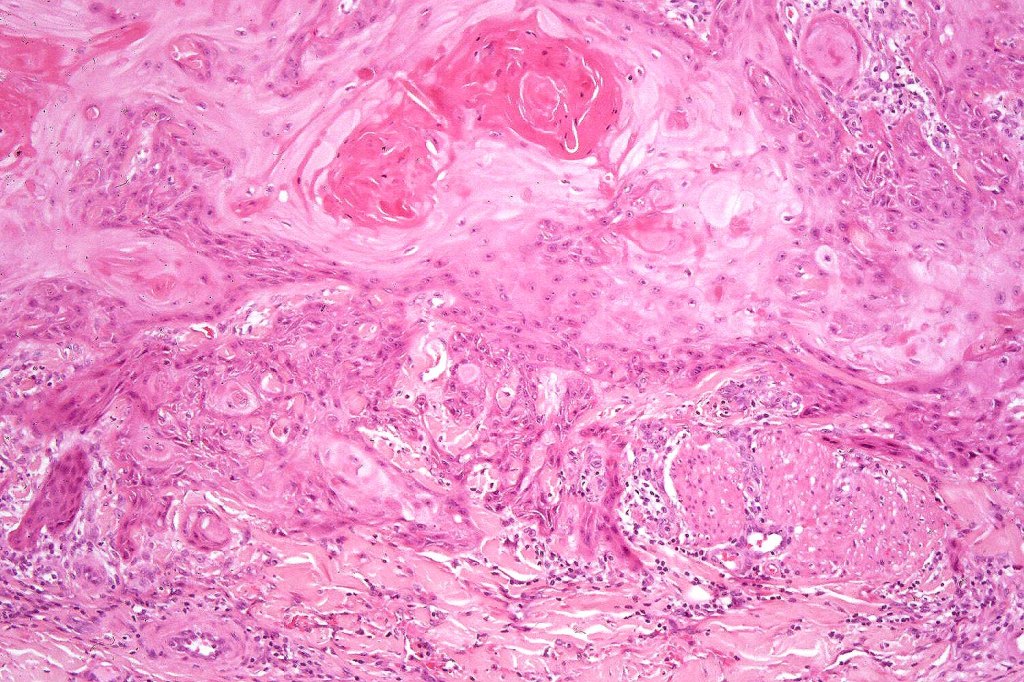

•Keratoacathoma (nowdays regarded as a variant of well differentiated squamous carcinoma) is characterized by a crateriform squamous epithelial lesion (dilated follicular infundibulum) with central keratin plug and adjacent collarette extending to the mid-dermis

•Well differentiated squamous epithelium often with a characteristic ground-glass appearance

•Only mild pleomorphism & basally located mitoses

•Neutrophil-rich microabscesses & necrosis

•Entrapped elastic fibers undergoing transepidermal elimination

Below is a fascinating case shared on McKee Derm by Dr. James Simpson. There is an obvious keratoacanthoma but at the edge of the lesion there is marked atypia with nuclear enlargement and pleomorphism. This is also evident in the adjacent epidermis and in the deeper nests.